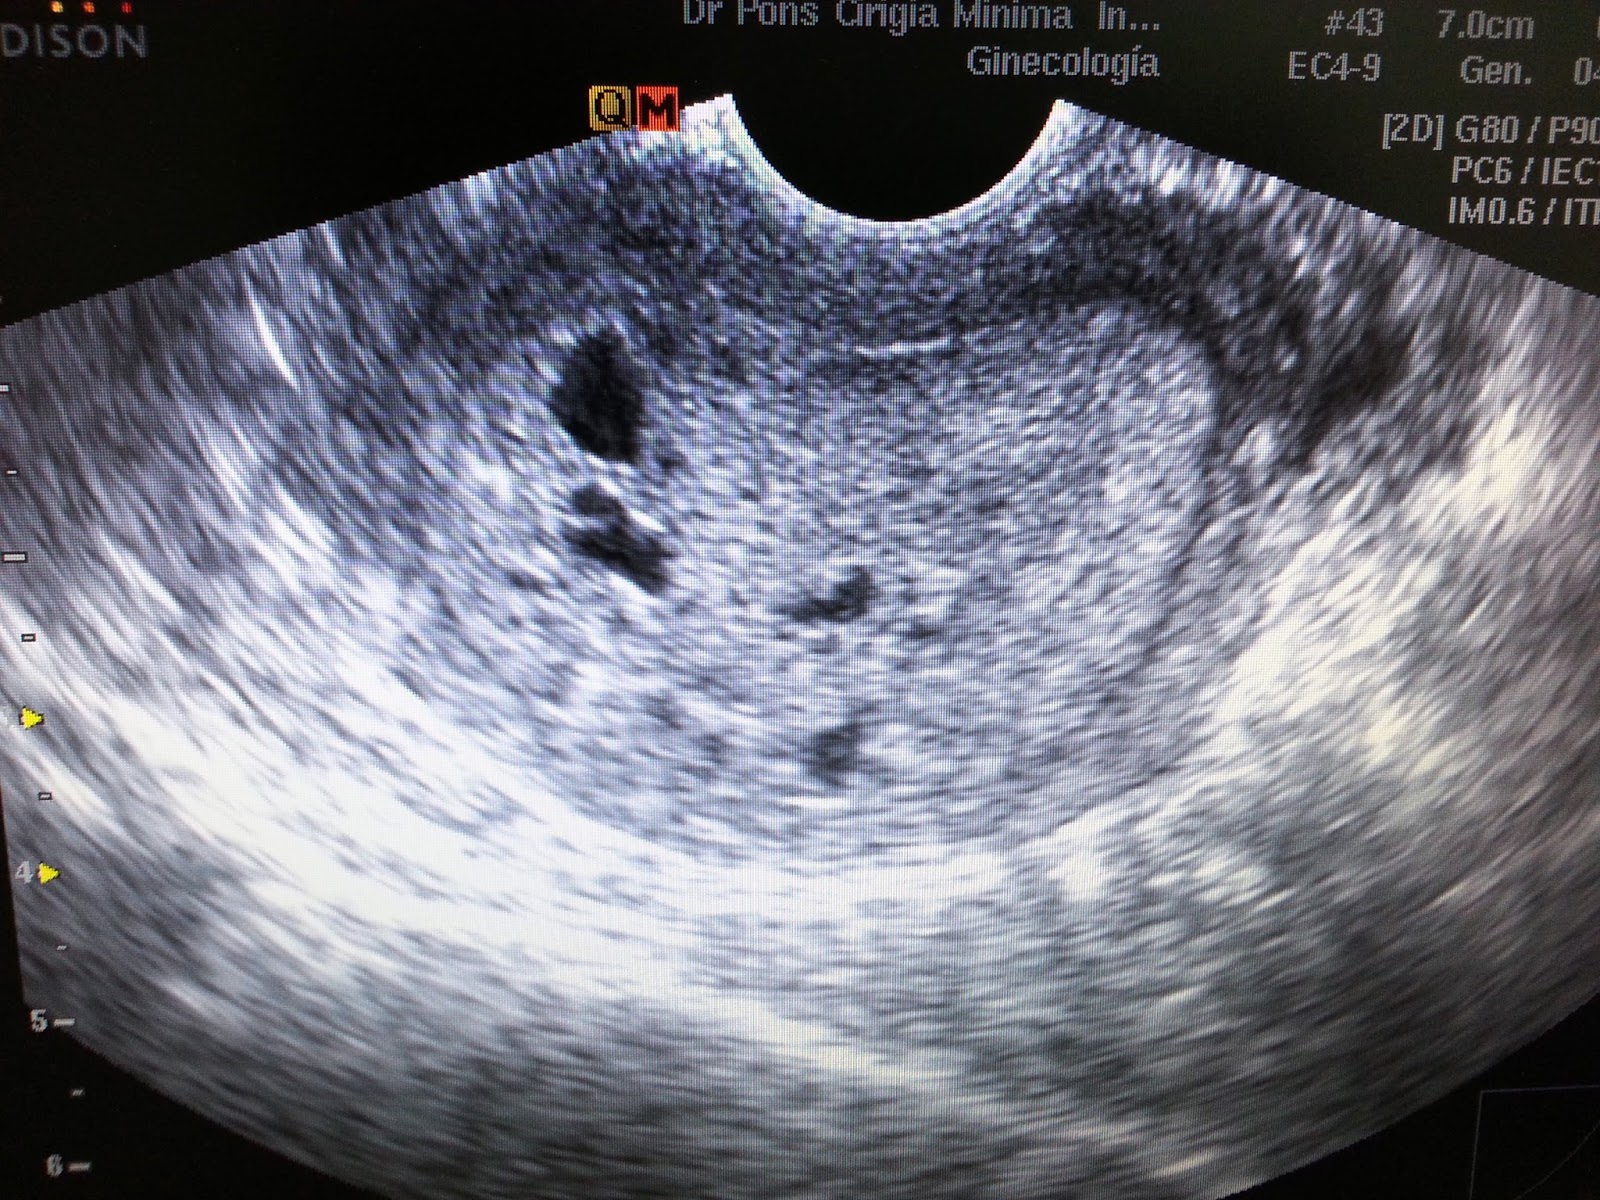

Cirugia Minima Invasiva Ginecologica Engrosamiento del endometrio. Que hago?

Técnica ecográfica del útero